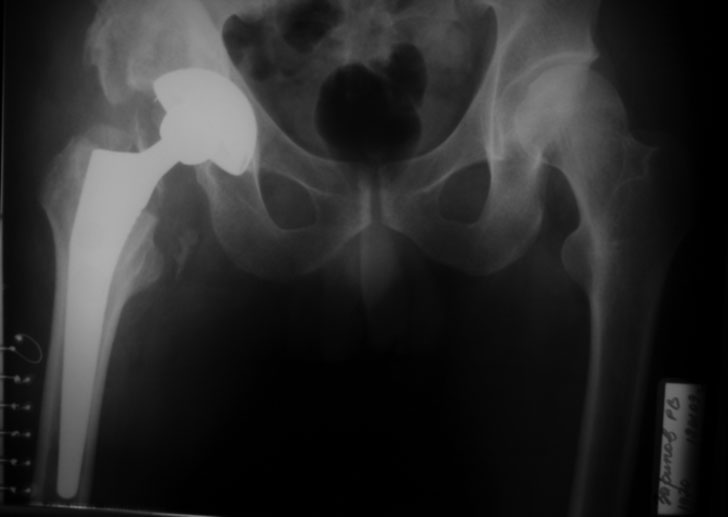

Застарелый вывих бедра (продолжение темы)

репозиция 3 нед, артропластика Corail-Duraloc